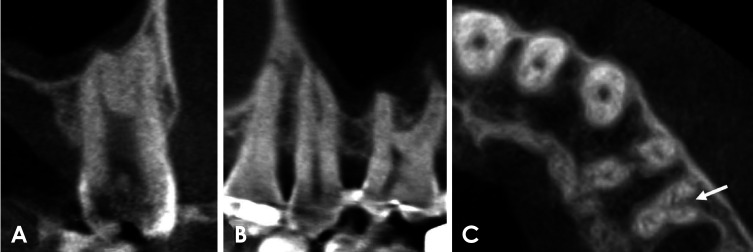

Purpose: This study aimed to evaluate the number of roots and type of root canals in maxillary first and second premolars within a selected Korean population utilizing cone-beam computed tomography (CBCT). Additionally, it sought to investigate potential differences in these features according to sex and tooth type.

Materials and methods: CBCT images of 585 maxillary first premolars and 578 maxillary second premolars from 303 patients were retrospectively reviewed. The number of roots was classified based on root morphology, and canal configurations were categorized into 8 types according to the Vertucci classification. For statistical analysis, chi-square or Fisher exact tests were employed to compare root number and canal morphology according to sex and tooth type.

Results: CBCT analysis revealed that 71.5% of maxillary first premolars and 97.6% of maxillary second premolars had 1 root. The most common canal configuration in maxillary first premolars was Vertucci type IV (42.6%), whereas type I predominated in maxillary second premolars (76.5%). Significant differences in root number and canal configurations were found between men and women (P<0.05), with single roots and Vertucci type I canals more commonly observed in women.

Conclusion: Both maxillary first premolars and maxillary second premolars typically had 1 root, with a smaller percentage possessing 2 roots. Significant sex differences were observed in root number and canal type. This study highlights the variability in root number and canal configuration, emphasizing the importance of recognizing these variations to achieve successful endodontic treatment.